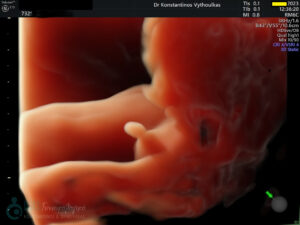

- Υπερηχογραφική εξέταση, η οποία συμβάλλει στη διαπίστωση της ενδομήτριας κύησης και αποκλεισμό της έκτοπης κύησης. Επιπλέον, μπορεί να διαπιστώσει εάν πρόκειται για μονήρη ή πολύδυμη κύηση, να ανιχνεύσει την εμβρυϊκή καρδιακή λειτουργία μετά τις 6 εβδομάδες και να προσδιορίσει υπερηχογραφικά την ηλικία κύησης, με βάση το κεφαλουραίο μήκος του εμβρύου μετά τις 8 εβδομάδες.